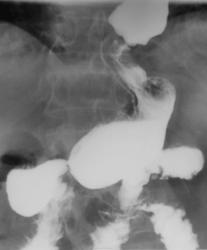

В настоящее время пациент утверждает, что пища не проходит. Лечащим врачом направлен на рентгенологическое исследование желудка.

По малой кривизне тотально цепочка танталовых швов, строение пищеводной трубки страноватое. Не было пластики пищевода чем-то, толстой кишкой, например?

Частичная резекция - кардиальный отдел желудка

Да цепочка есть. Пластики не было.

По правой стенке пищевода определяется дефект наполнения, но после опорожнения пищеводной трубки вроде бы все становится ровным-сдавление органа из-вне? Чем? Пакетом лимфоузлов, конгломератом мягких тканей в результате тяжелого спаечного процесса? Или стеноз абдоминального отдела (если только не убирали верхнюю треть в области кардии и нижний отдел пищевода)?

В выделенном участке пищевода расширенные складки, наверное они потеряли эластичность. В проксимальном направлении расширение пищевода и ,вероятно, с нарушением паасажа. Привратник сужет, возможно функциональное.